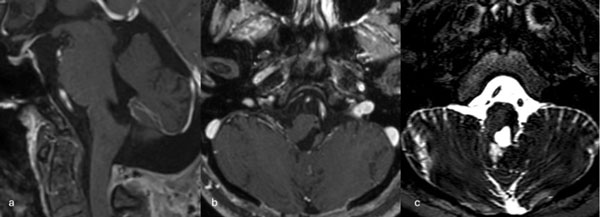

Figura 6. RM preoperatoria de encéfalo. Se evidencia una lesión única intraaxial localizada en el puente y pedúnculo cerebeloso medio izquierdo, hiperintensa en T1 y con un anillo hipointenso en T2, característica de una malformación cavernomatosa con sangrado reciente. A) Imagen ponderada en T1 en corte sagital. B y C) Imágenes ponderadas en T2 en cortes axial y coronal, respectivamente.

Figura 3. RM preoperatoria de encéfalo. Se evidencia una lesión única intraaxial centrada en puente y pedúnculo cerebeloso derecho, sugerente de un cavernoma roto. A, B y C) Imágenes ponderadas en T2 en cortes sagital, axial y coronal, respectivamente, donde se observa un importante hiperintensidad perilesional, sugerente de edema.